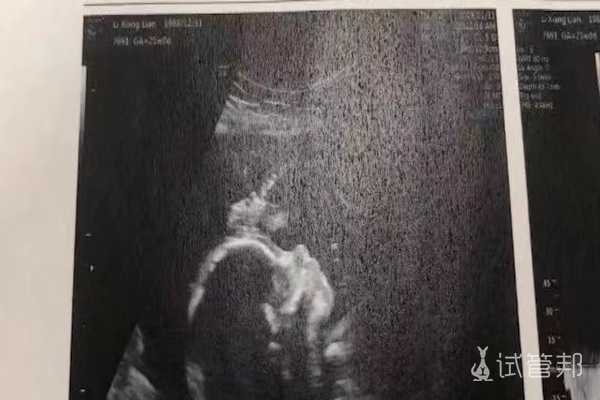

我是做的第三代试管婴儿,取卵3次,前2个囊胚不合格。第3次,有5个合格的囊胚,进行了1次移植,最后成功怀孕了。怀孕3年,在试管路上也遇到过很多不孕不育的女生。结合我和..

我是在武汉大学人民医院做的三代试管婴儿,已经确认成功好孕了,翻倍情况也很好,现在就等着宝宝能够顺顺利利的到我们家里来。下面能也跟姐妹们分享一下我做三代试管的一些..